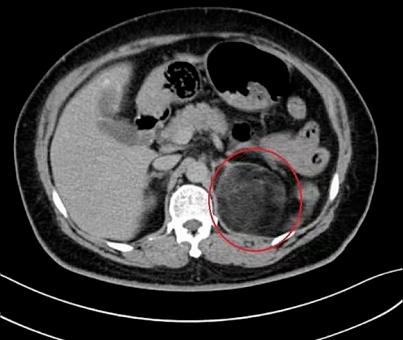

贵航三〇〇医院泌尿科主任李永光说,患者丁女士,住院前是比较肥胖,而且这个肥胖已是好多年了,通过查体发现左侧肾上腺长了一个巨大的肿瘤。初步判断这个肿瘤是造成她肥胖和血压高的罪魁祸首。

尤其是最近这段时间,丁女士的血压一直是居高不下,这让她意识到问题的严重,不得不住院治疗。医生一检查,丁女士肾上腺的肿瘤已经长到8了厘米,已经严重影响压迫肾脏,需要进行手术摘除。

经过一个星期的精心准备,2月26号,医生对丁女士实施了手术,从丁女士肾上腺上摘除了8厘米大的肿瘤。